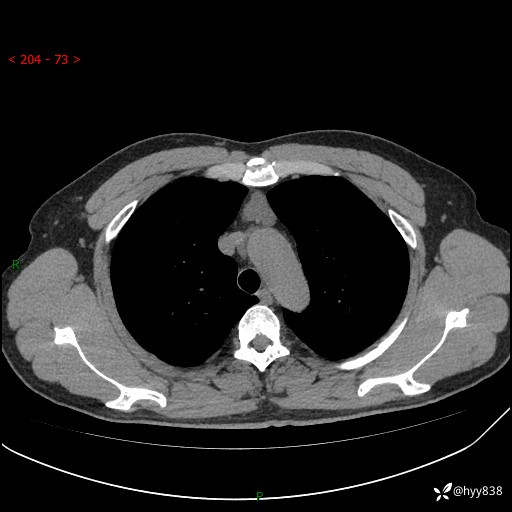

患者性别:女

患者年龄:49岁

简要病史:跟骨骨折,常规CT发现纵隔占位

胸部CT平扫

增强(动脉期+静脉期)